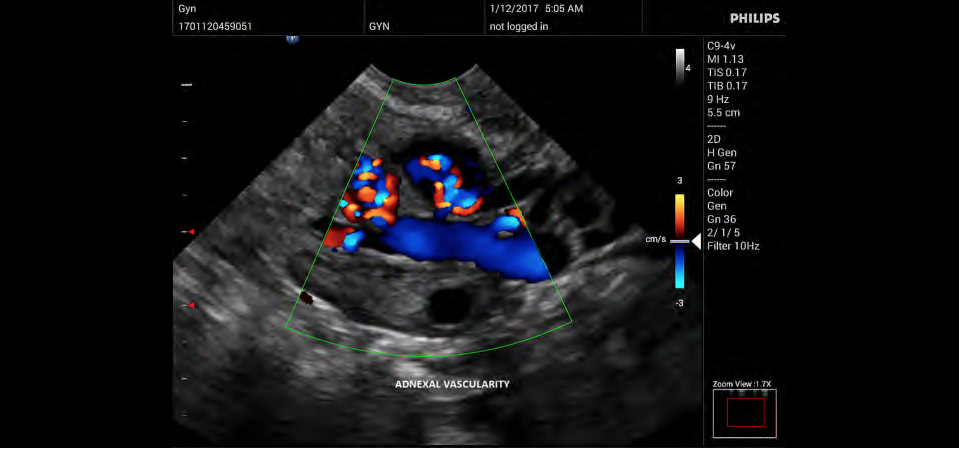

• Цветное допплеровское картирование

• Направленный энергетический допплеровский режим: Дополнительно к возможностям визуализации сосудов в стандартном энергетическом режиме добавляется информация о направлении. Этот режим полезен для визуализации мелких сосудов в качестве замены цветного допплеровского картирования.

• Конвексный УЗИ датчик Philips C9-4v